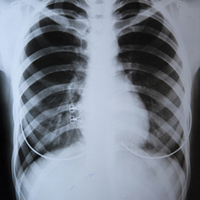

В Україні у середньому близько 70 днів триває лікування пацієнтів із туберкульозом у стаціонарі, майже 70% нових виявлених хворих підлягають госпіталізації.